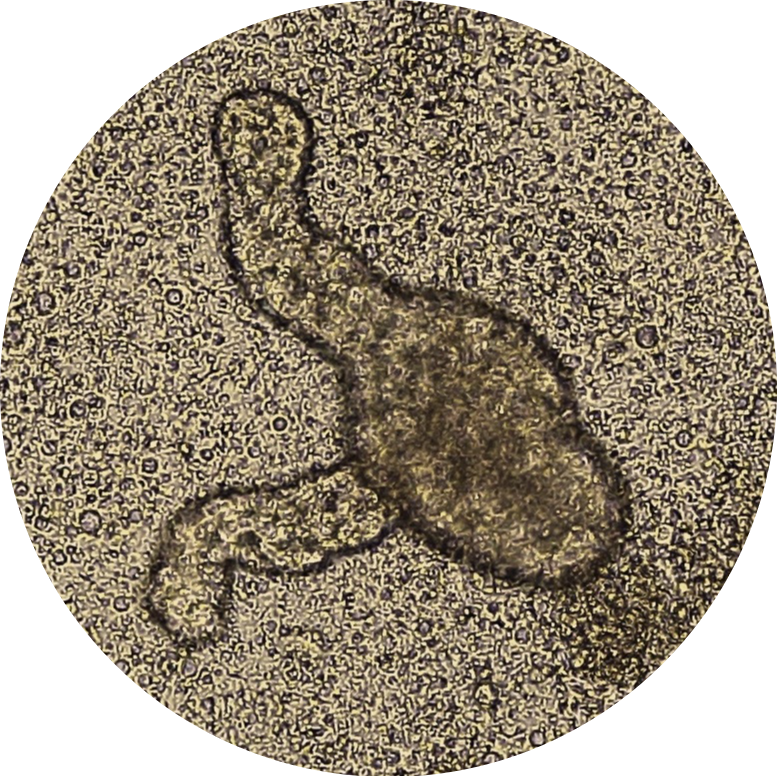

These organoids mimic the structure and cellular diversity of human intestinal epithelium.IPSC-derived intestinal products show a crypt-like structure, which is the common feature of intestinal epithelium. They contain enterocytes, goblet cells, Paneth cells, and enteroendocrine cells. They are valuable tools for studying gut barrier function, host-microbiome interactions, screening drugs, assessing pharmacokinetic profiles of potential medications, and testing the toxicology of possible interventions.